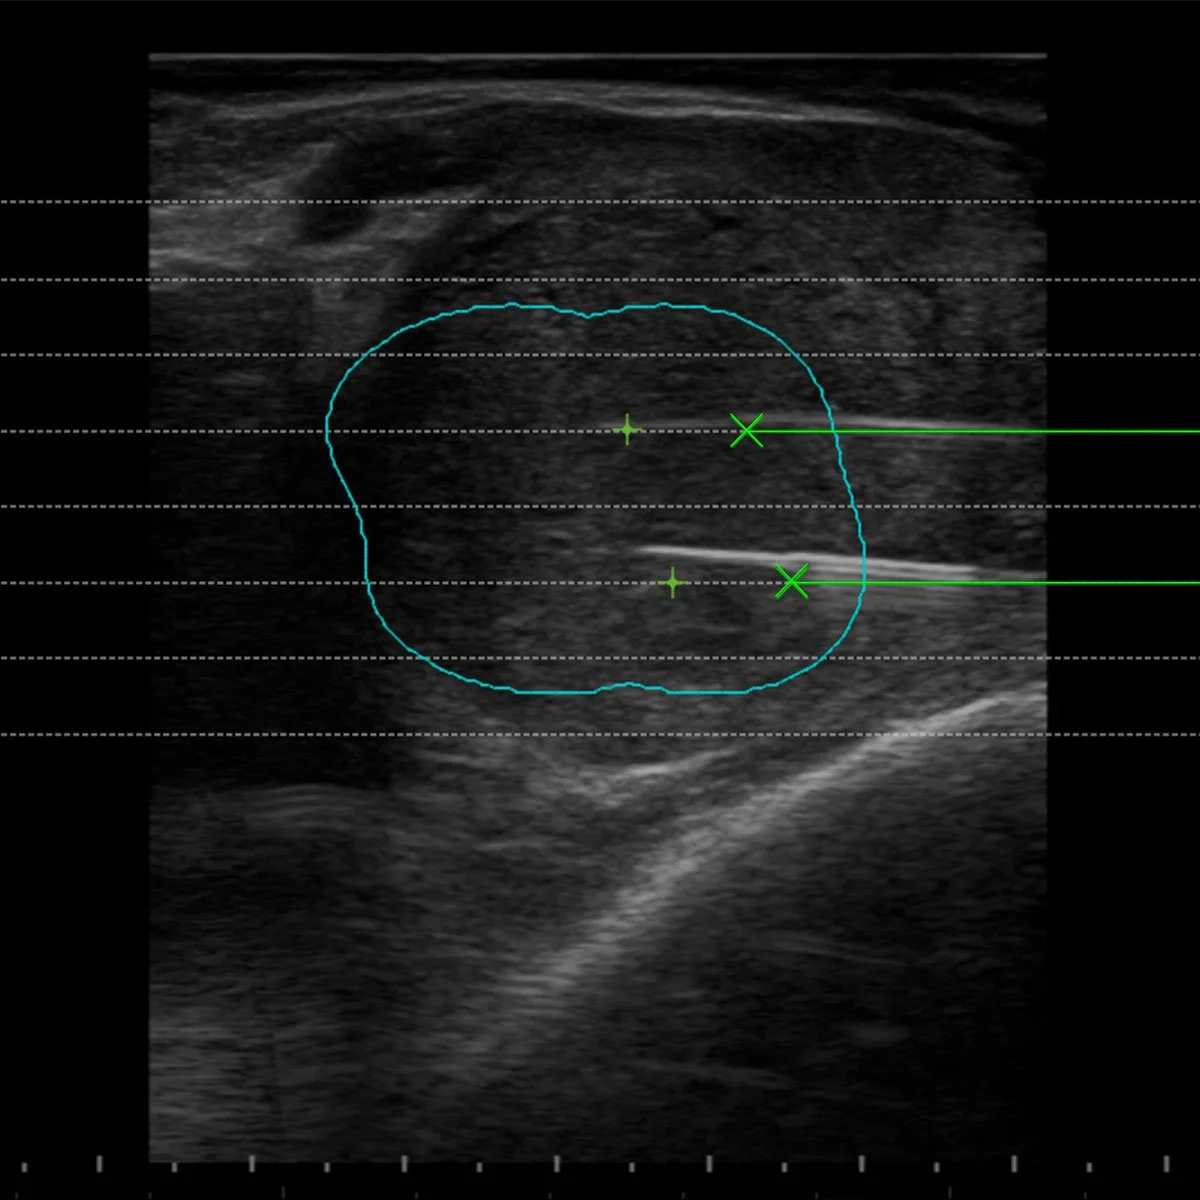

Guiding Systems and dedicated Biopsy Software

The Guiding Systems on the Esaote probes have been designed for each kind of application to help the operator when positioning several fibres inside the lesion to be treated. The dedicated Biopsy Software for EchoLaser Thermal Ablation inside the US unit displays the guidelines on the screen for each different guide in order to allow for an evaluation of the best positioning of the applicator in reference to the size, morphology and position of the lesion.

Pre-treatment Planning Software

The Planning Software allows the operator to choose the safest needles insertion paths and the most suitable among various treatment options (number of fibers, pull-back number and applicators distance) for each specific case.